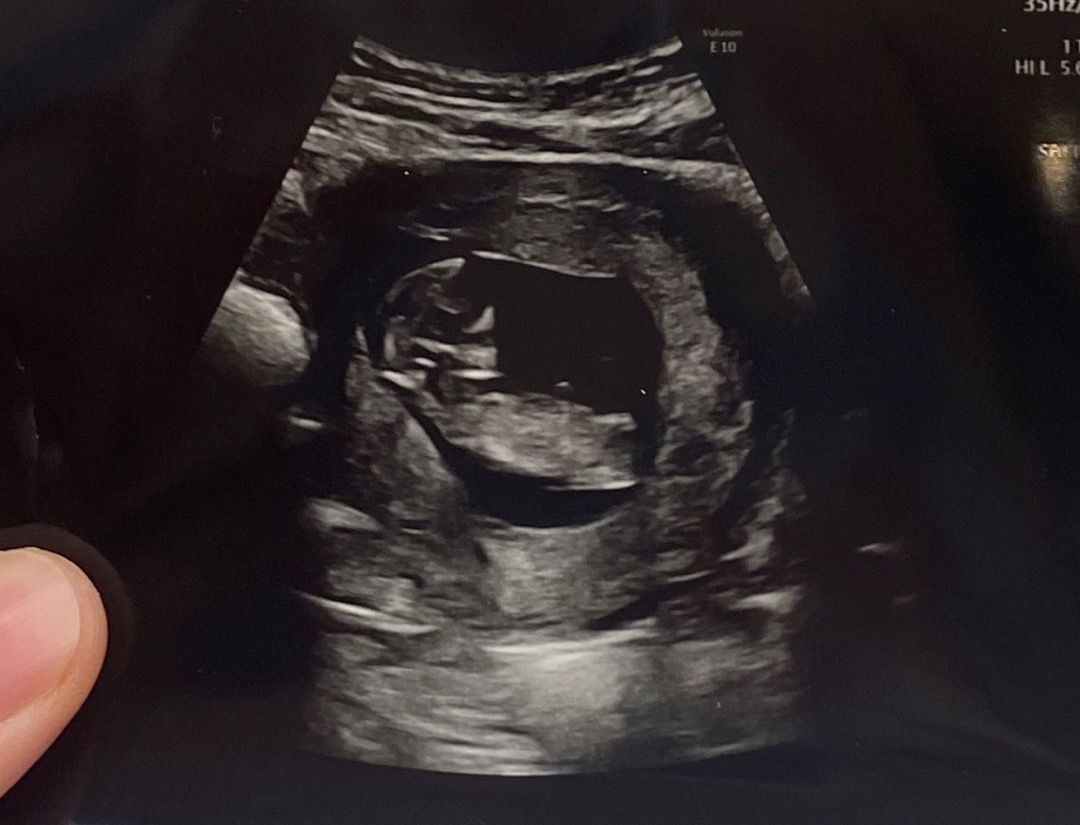

11주 6일 초음파 보고 왔어요

각도법으로 알 수 있다는데 각도법 잘 보시는 고수님들 저 아들일까요 딸일까요?? 너무 너무 궁금해요~~~